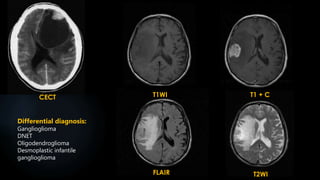

CECT T1WI

FLAIR T2WI

T1 + C

Differential diagnosis:

Ganglioglioma

DNET

Oligodendroglioma

Desmoplastic infantile